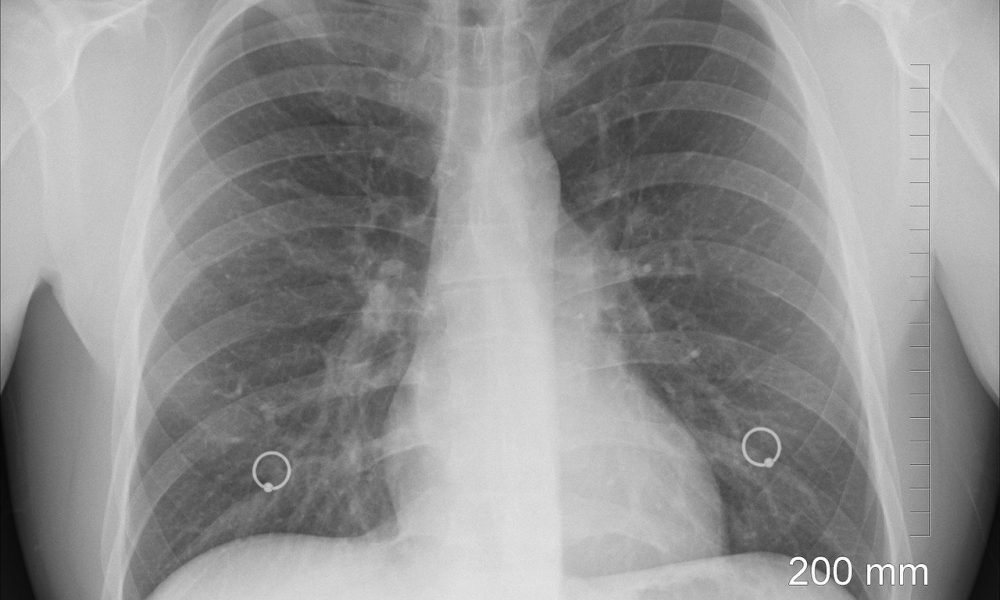

In an ongoing effort to enhance COVID-19 testing capabilities, innovative technologies are continually emerging, as companies leverage advanced techniques to determine virus infections. A recent development from Aspenstate involves a portable X-ray system, called AirTouch, which has received FDA approval, marking a significant step in the realm of digital health diagnostics.

The AirTouch system promises to facilitate rapid chest X-rays for potential COVID-19 patients, significantly streamlining the diagnostic process. Weighing merely 5.5 pounds (2.5 kg), the device resembles a large touchscreen digital camera. Users can capture images at the push of a button, and these images can be wirelessly transmitted to a clinical image storage system or PACS, without requiring a computer. The device’s battery can be fully recharged in just two hours and is capable of taking up to 300 images on a single charge.

Given its portable nature, the AirTouch system has already shown utility in COVID-19 screening operations in South Korea. As stated by David Lee, Vice President and COO of Aspenstate, “Our customers have seen a dramatic increase in their capacity and the ability to transport patients quickly and efficiently.”

Lee further highlighted that the integrated software makes the device user-friendly, enabling its deployment beyond traditional radiology settings. The potential applications for the AirTouch extend to emergency facilities, ambulances, sports medicine, and even veterinary practices, suggesting a broad impact on healthcare delivery amidst the pandemic.

With innovations like the AirTouch, the landscape of COVID-19 diagnostics is evolving rapidly, promising to enhance patient care through advanced technology and improved accessibility.